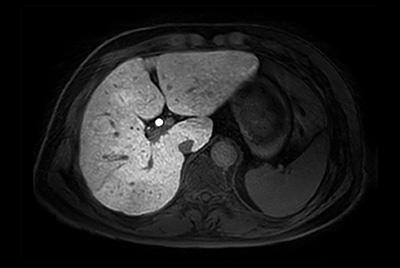

SmartSpeed Liver